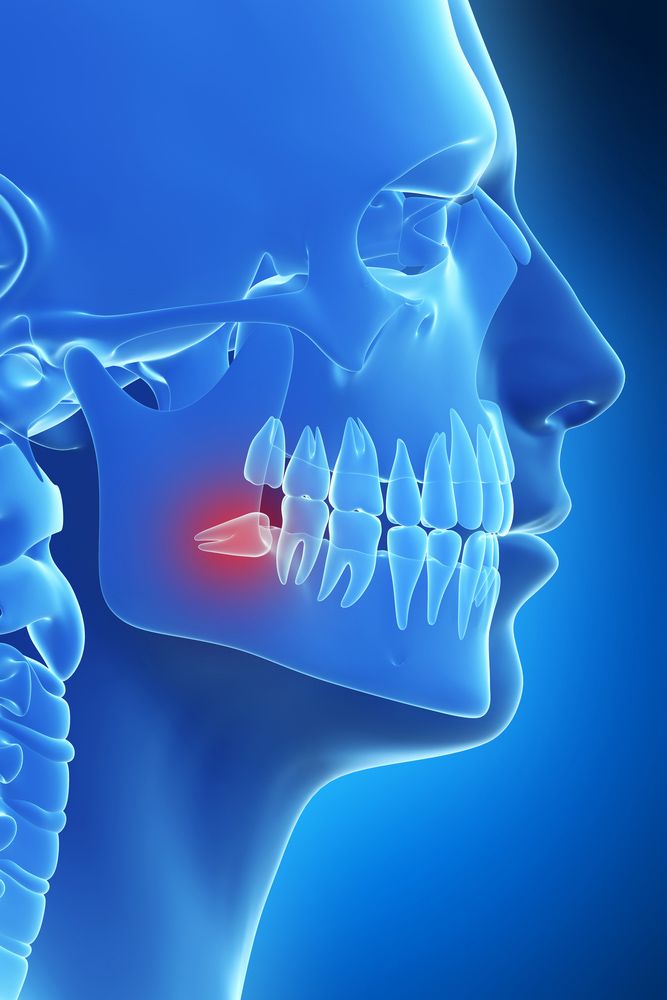

Wisdom Tooth Removal

Dr. Sean Healy and Dr. Diego Hurtado use advanced techniques to minimize discomfort and healing time after wisdom tooth removal. Sedation can ensure your comfort and platelet-rich fibrin, containing growth factors, naturally stimulates the healing process. At a follow-up appointment, one of our surgeons will monitor your recovery.